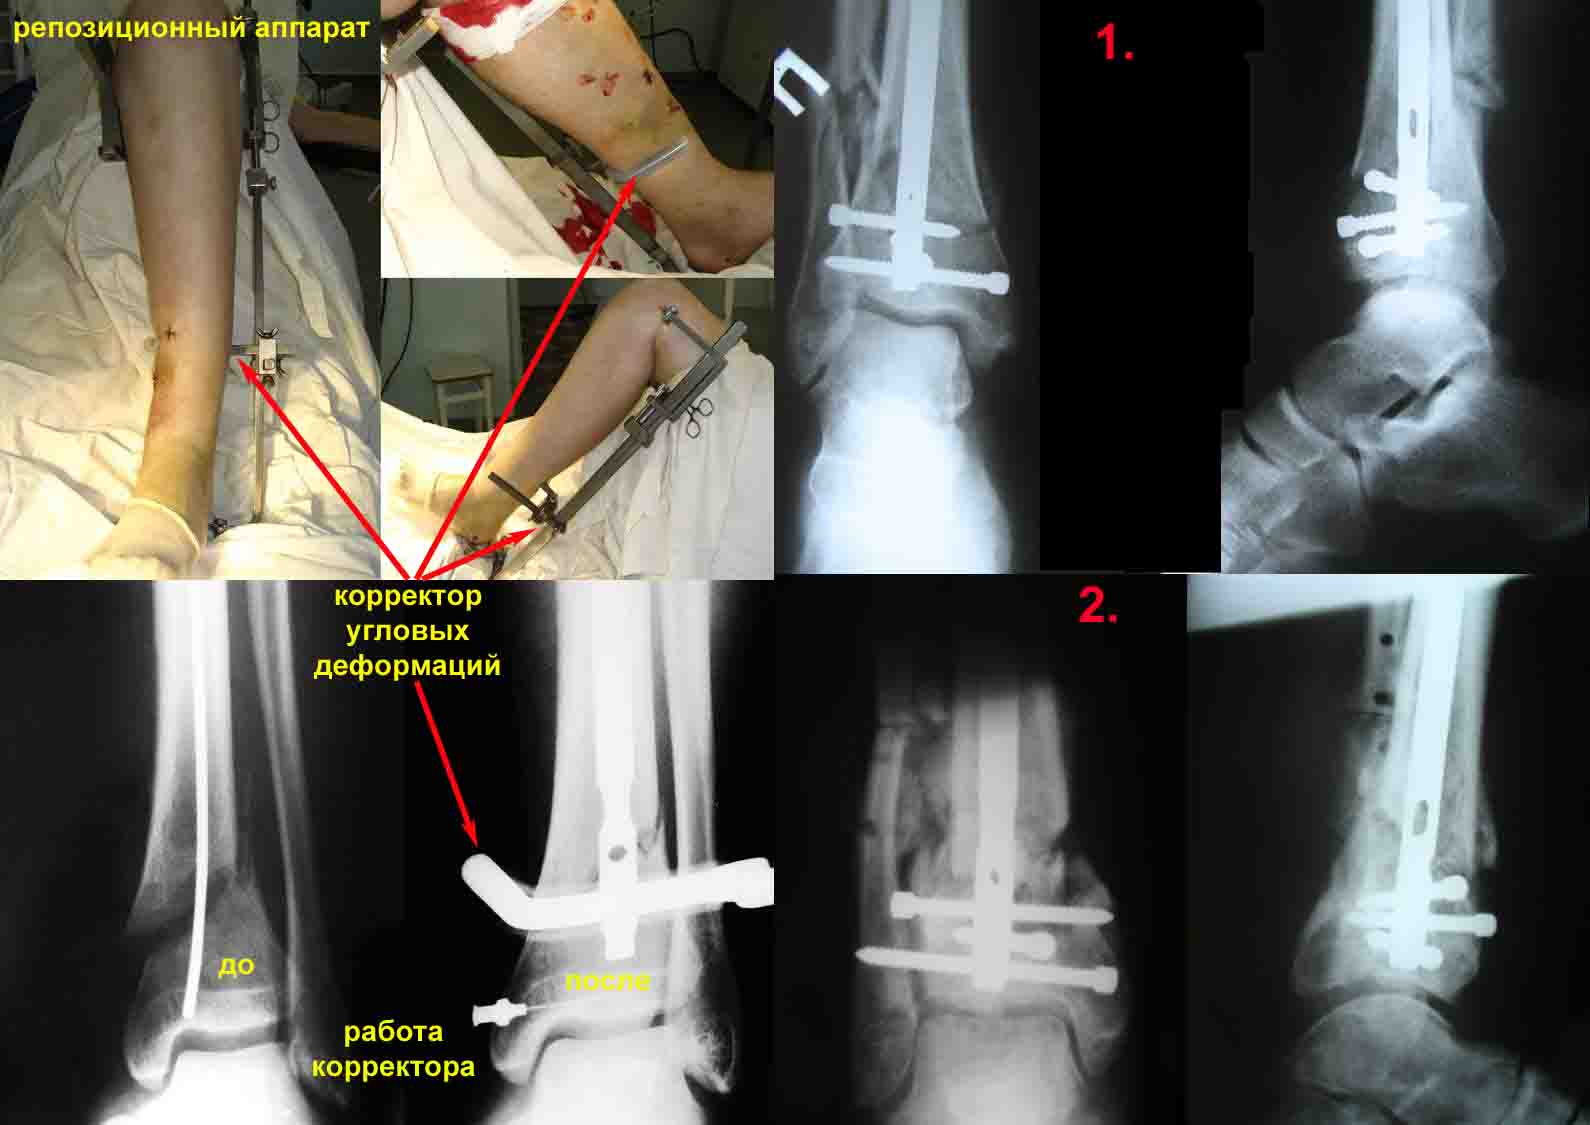

1.      использование спицевого репозиционного аппарата для предварительной репозиция костных отломков на операционном столе и удержание костных отломков в репонированном положении на протяжении всего времени оперативного вмешательства.

Для примера – вложенный файл. Фотографии репозиционного аппарата и работа корректора угловых деформаций.

Механическое прицельное устройство для дистального блокирования предназначенное для проведения блокирующих винтов канюлированных стержней в разных плоскостях без ЭОПа (и вообще без применения рентгентехники) с успехом применяется нами, на протяжении вот уже десяти лет. (Рентгенограммы 1 и 2)